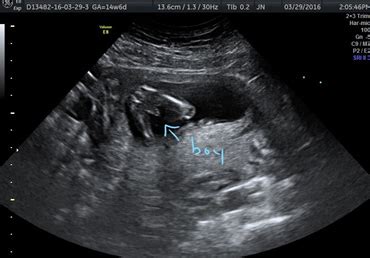

La finalul lunii a noua, bebelușul tău atinge dimensiunea unui pepene dulce. Cu fiecare zi ce trece, micuțul se pregătește pentru debutul în lumea exterioară, iar tu vei simți fiecare mișcare și bătăi de inimă. În luna a noua, bebelușul dobândește toate reflexele esențiale, inclusiv reflexul de supt, Moro, de a apuca și de înghițire. Aceste abilități îl vor ajuta să se adapteze rapid la mediul extern după naștere. După săptămâna 37, bebelușul este considerat la termen. Este gata să vină pe lume, dar rămâi pregătită pentru orice surpriză și să ai totul pregătit pentru sosirea lui. În această fază, bebelușul primește anticorpi de la mamă, pregătindu-l pentru a lupta împotriva infecțiilor imediat după naștere. Este un dar valoros pe care îl primește pentru a-și întări sistemul imunitar.

În această perioadă, bebelușul poate să-și reducă activitatea, dar vei simți mișcările lui zilnic. Este momentul perfect să te conectezi emoțional cu micuțul și să te pregătești pentru marea întâlnire. Cu toate acestea, dacă observi o reducere semnificativă a mișcărilor fetale, este recomandat să te adresezi medicului pentru monitorizare. Lipsa mișcărilor poate fi și un semn că bebelușul este în perioada de somn profund, dar este important să te asiguri că totul este în regulă.